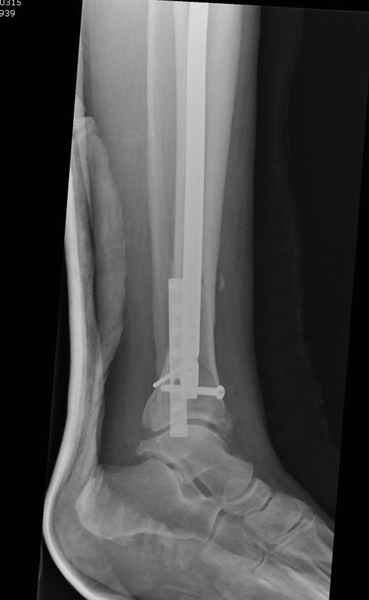

Здесь мы использовали новый Synthes Nail с дополнительными дырками, в проксимальной части 4: по две косых и поперечные (один стандартный а другой динамический), в дистальной части две поперечные, прямая и косая. Вес больного более 120 кг, нагрузку начнем через месяц.